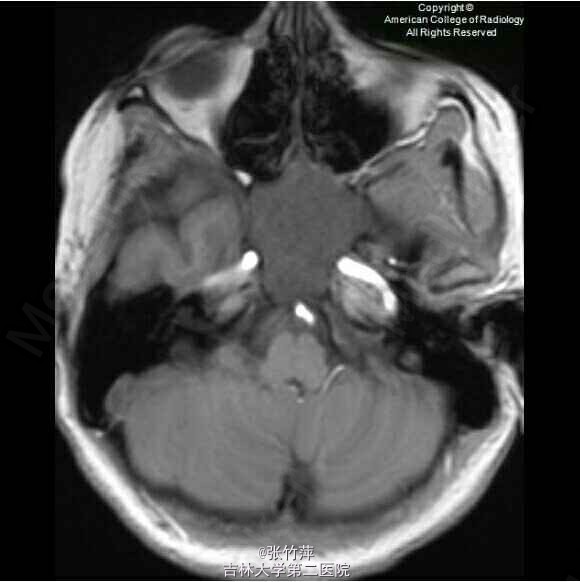

女,20岁。头痛一月余,伴复视,流泪,视力下降。

脑部磁共振图片如下

蝶窦粘液囊肿